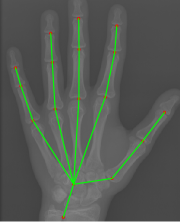

Refer to caption

Figure 1: (a) Original image. (b) Hand keypoint annotation used in BoNet [2]. (c) We convert the keypoints to bounding boxes which are used in our method to learn hand structure and extract local information.

The original annotations of hand pose are a series of points, and we need to use boxes for local extraction. Hence, during the training time, we replace the point annotations by boxes centered at the points (Fig. 1). We use the same loss function as in [13] to train RPN, and we denote the loss function of RPN as LRPNsubscript𝐿𝑅𝑃𝑁L_{RPN}.